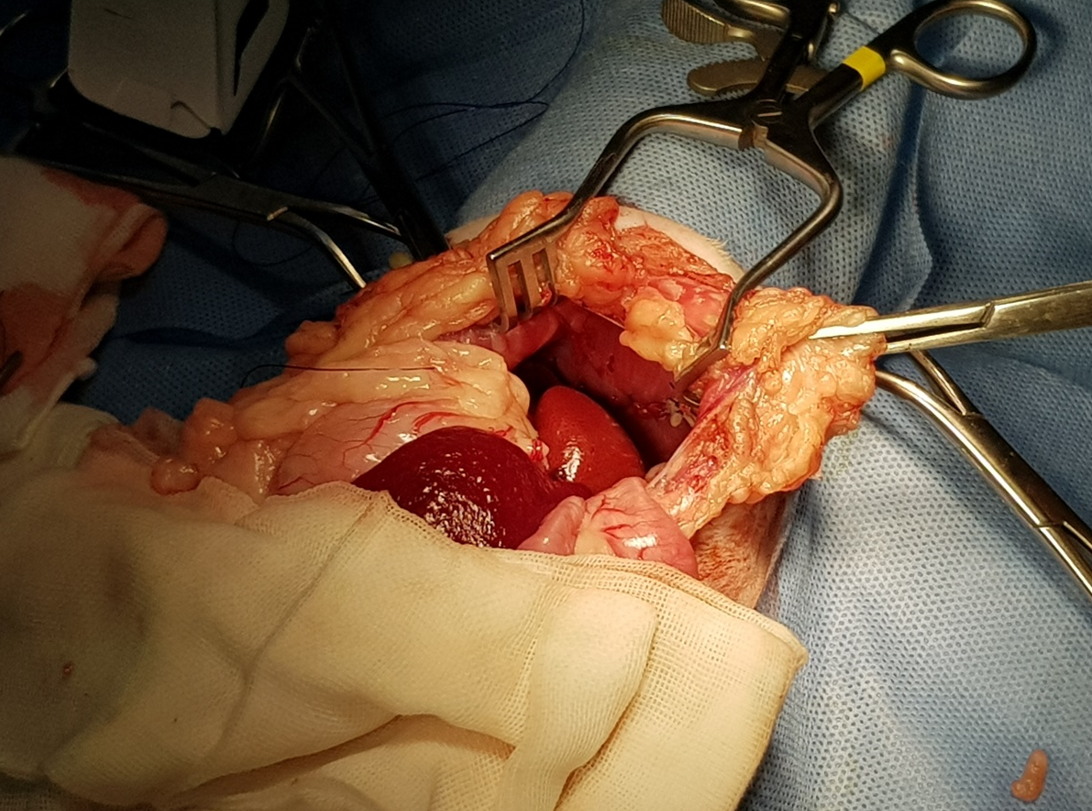

手術過程

開腹後發現肝臟從腹腔掉到胸腔內,橫膈破了一個大洞

將橫膈修補起來,看到破洞縮小很多

看到橫膈膜全貌

將胸腔內的空氣抽掉讓肺臟可以正常的擴張